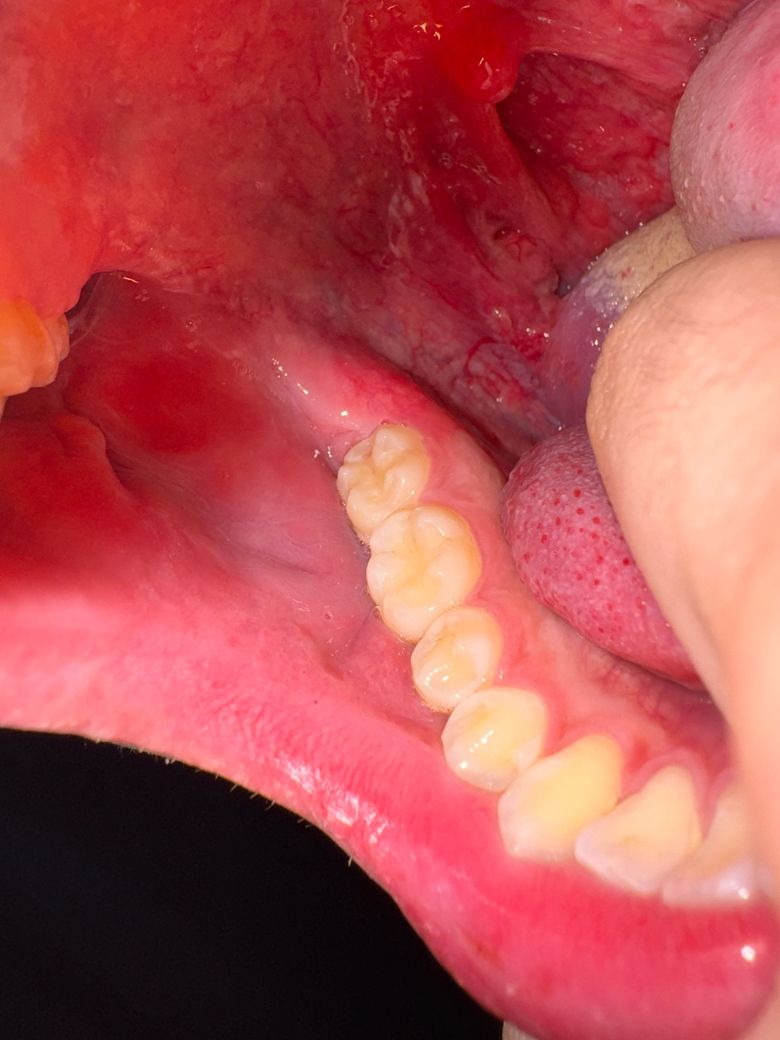

• 2번 째 사진

• 사진상 위치는 혀 옆면 하부, 구강저 부위로 보이며, 점막이 약간 돌출되고 주변 혈관이 확장되어 보입니다. 통증이나 이물감이 없는 점을 고려하면 급성 염증성 병변보다는 양성 변화 가능성이 높습니다.

가장 흔한 원인은 다음과 같습니다. 첫째, 점액낭종으로 침샘관이 막히거나 손상되면서 점액이 고여 작은 혹처럼 보일 수 있습니다. 무통성이고 투명하거나 붉게 보일 수 있습니다. 둘째, 국소 혈관 확장 또는 경미한 점막하 출혈입니다. 혀를 씹거나 자극이 반복되면 혈관이 도드라져 보이거나 멍처럼 보일 수 있습니다. 셋째, 섬유성 증식으로 반복 자극에 의해 살짝 솟은 조직이 생기는 경우입니다.